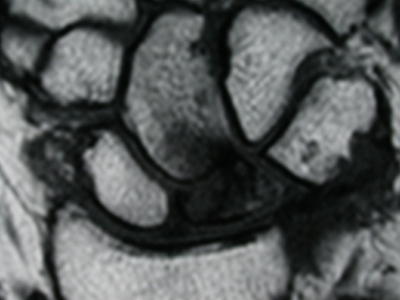

Durchblutungsstörung des Mondbeins im Frühstadium

Der Beginn der Erkrankung verläuft oft ohne Schmerz oder andere Symptome und wird dann meist als Zufallsbefund bei Röntgenaufnahmen oder einer Kernspintomographie festgestellt. Ab dem Stadium II bestehen Schmerzen im Handgelenk bei Belastung, aber auch spontan und im Ruhezustand. Mit fortschreitender Erkrankung werden die Schmerzen stärker und die Beweglichkeit im Handgelenk mehr und mehr eingeschränkt. Nach Zerfall des Mondbeins im Spätstadium kann der „karpale Kollaps“ eine Folge sein: Der an das Mondbein angrenzende gesunde Handwurzelknochen verschiebt sich und kann zu einer Einsteifung des Handgelenks führen.

Stadium I: Nur im Kernspintogramm aufgrund der dann sichtbaren Ödembildung diagnostizierbar

Stadium II: Im Röntgenbild ist eine höhere Dichte des Knochens zu erkennen, evtl. zeigen sich auch erste Frakturlinien. Im Kernspintogramm sieht man eine inhomogene fleckige Zeichnung.